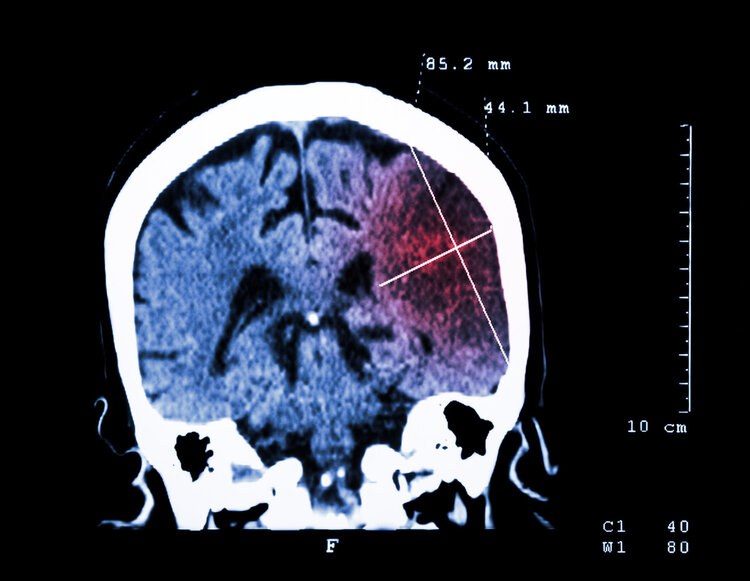

报告指出 , 在2016年的1370万脑卒中新发病例中 , 中国占555万例 , 成为全球卒中发病人数最多的国家 。

《中国脑卒中防治报告(2015)》数据显示 , 我国40岁以上人群有15%的人面临脑卒中高风险 , 发病率不断上升 , 高达354例/10万人 , 且有年轻化趋势 。

而在欧美国家 , 脑卒中的发病率正在呈下降趋势 , 其中 , 美国的脑卒中发病率在上世纪就开始有下降趋势 。